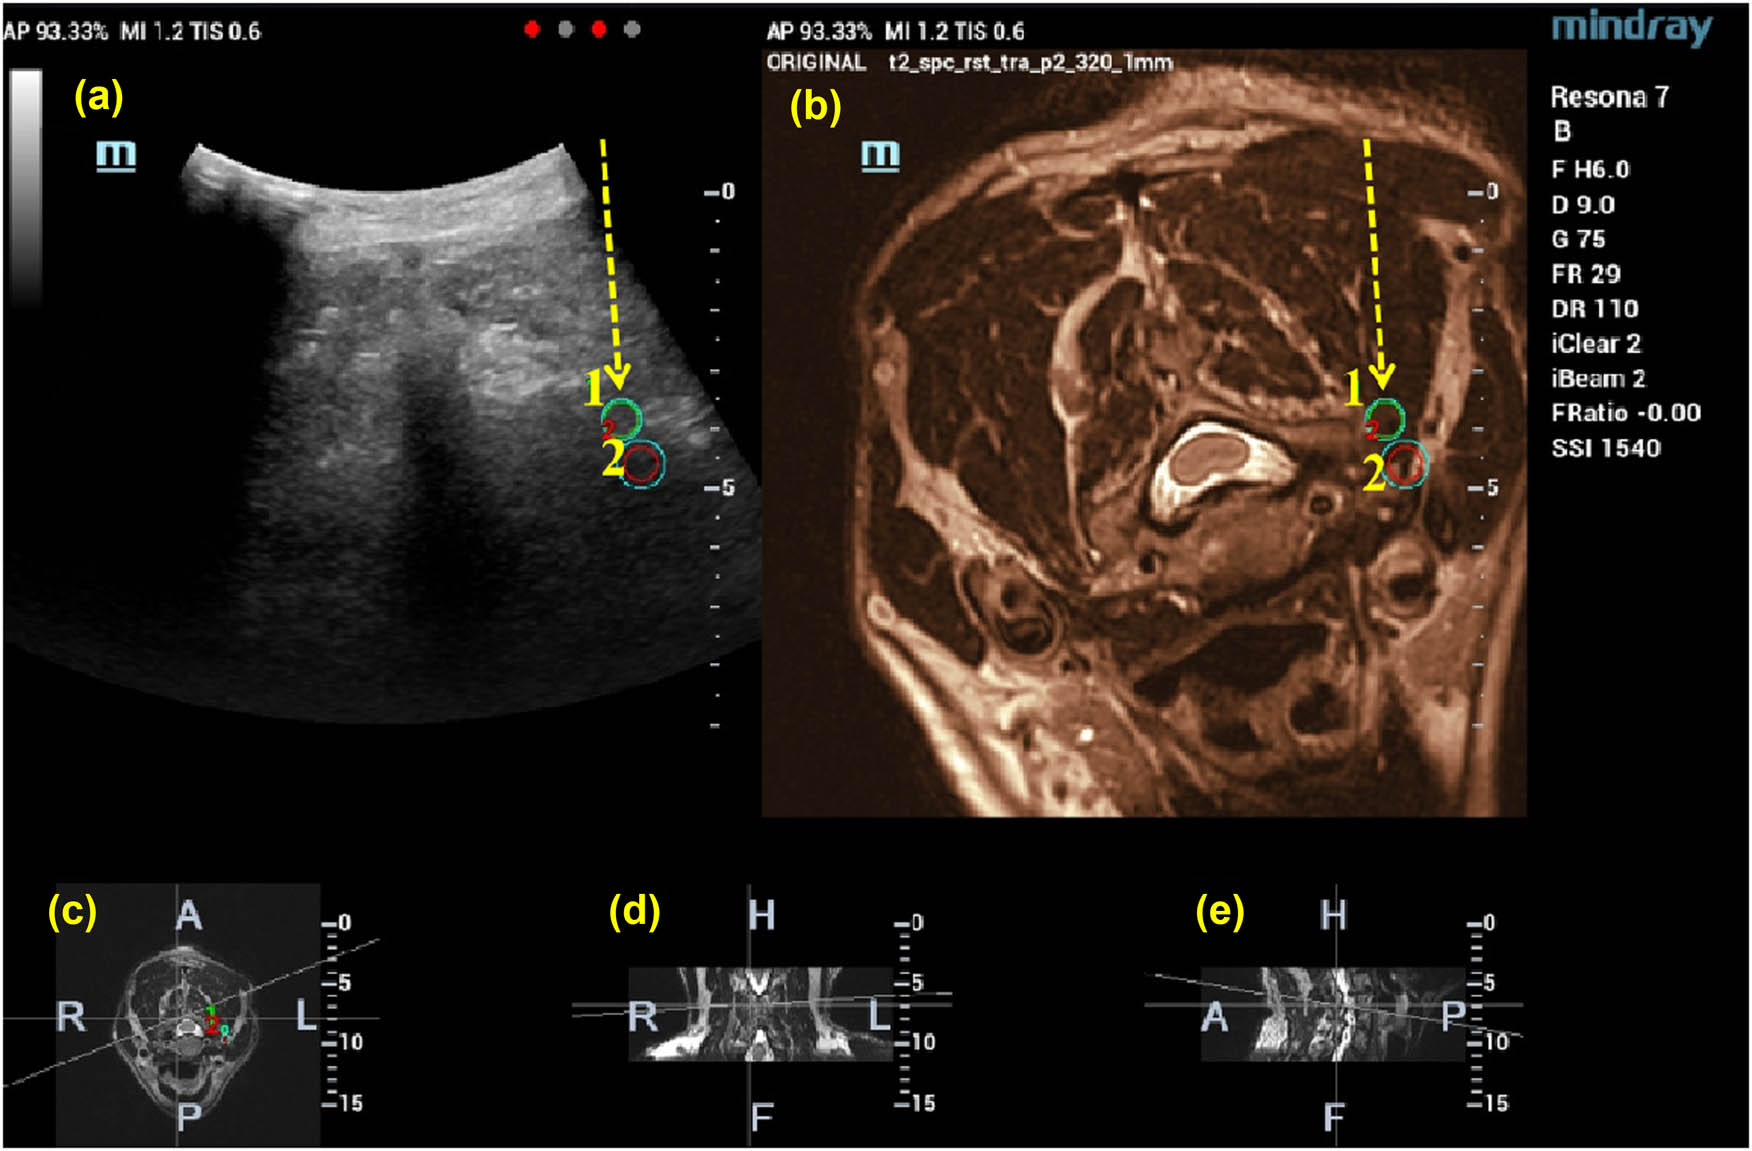

The connection of the magnetic transmitter facilitated the activation of the image fusion mode. Image registration was achieved by aligning the MRI images with the ultrasonic probe’s imagery and the adjustable screen, utilizing surface markers, bone landmarks, nerves, and other anatomical features as references for accurate matching (Figure 1).

The intended therapeutic target was pinpointed on the MRI images, guiding the formulation of a puncture trajectory based on the anatomical structures adjacent to the target (Figure 2).

Images of cervical vertebrae after US-MRI fusion: (a) US-MRI fusion images, (b) MRI images, (c) cross section, (d) coronal section, and (e) sagittal section.

The therapeutic target is marked on the MRI image, and the location of the target is also displayed on the fused image at the same time (1, 2). Then, the puncture path is designed according to the MRI and US images (shown by the yellow arrow). (a) US-MRI fusion images, with green circles indicating the target puncture points, (b)MRI images, (c) cross section, (d) coronal section, and (e) sagittal section.